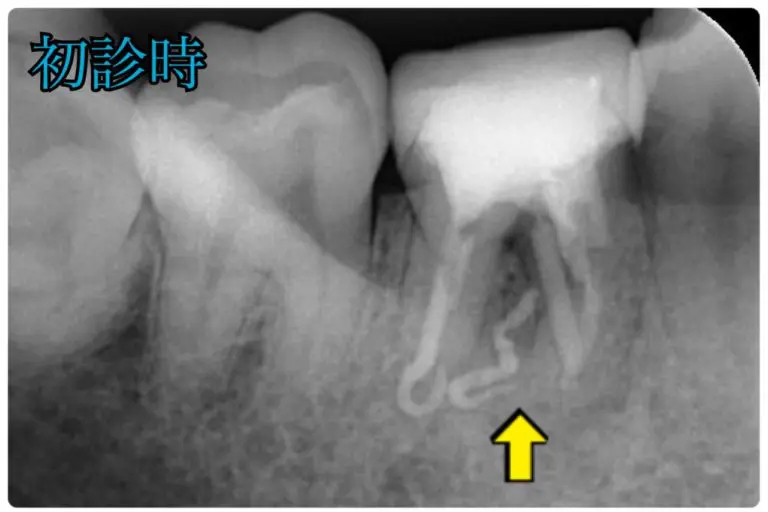

根管治療を続けるが膿が止まらない患者様

術前

術後

| 年代/性別 | 30代/女性 |

|---|---|

| 症状 | 6年前に根管治療をした歯から膿が出ており、再根管治療を5ヶ月ほど続けるが治らない。 |

| 費用 | 初診診断料:¥16, 500

感染根管治療:¥143, 000 リトリートメント:¥44, 000 パーフォレーションリペア:66, 000 ファイバーコア:¥38, 500 オールセラミックス:¥187, 000 |

| 備考 | メリット:将来的に歯を保存出来る デメリット:歯科医師に高い技術が求められる |